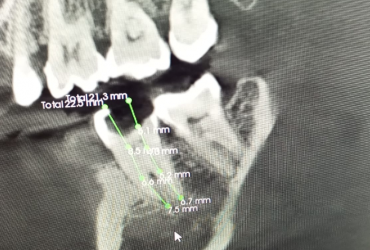

Galería

Algunos de nuestros tratamientos de endodoncia que permiten salvar piezas dentales, eliminar infecciones y devolver la salud y funcionalidad a tu sonrisa.